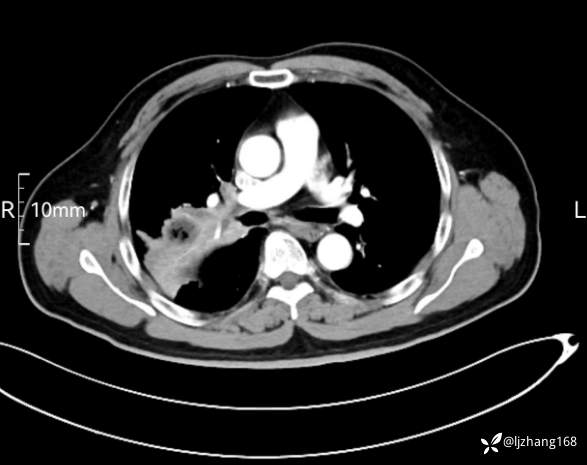

中年男患,右肺团片影,炎症0R肿瘤?

辅助检查:糖化血红蛋白12.3%。肺炎支原体IgG、IgM、呼吸道合胞病毒均未见明显异常。胸部CT:右肺上叶阻塞性肺炎。